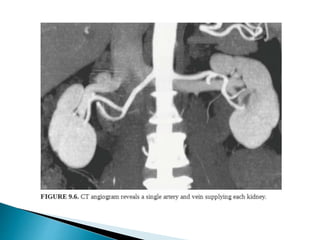

 CT is the preferred imaging due to better spatial resolution

and sensitivity to vascular calcifications and renal stones.

 CTA >> MRA

1. Distinguishing single/two main renal arteries.

2. Anatomy and to identify the point at which first branch

occurs.

3. Renal venous anatomy,

4. Tiny polar accessory arteries.